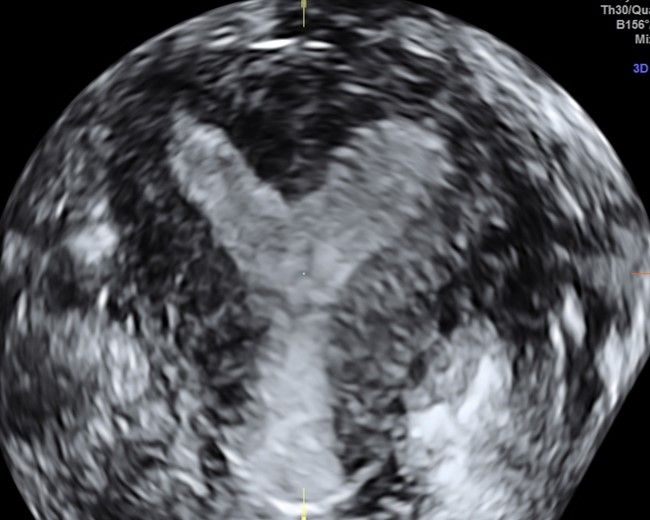

Современные экспертные УЗИ сканеры дают возможность проводить исследования всех органов в 3D. Это позволяет, используя полученный массив данных, получать диагностические сечения в любой плоскости, недоступной для обычного 2D УЗИ. Наиболее интересной является фронтальная. Например, визуализация полости матки. Диагностическая возможность выявления пороков развития превосходит все другие методы (рентгеновские и МРТ). Метод также позволяет уточнить положение ВМК (спирали) в полости матки, расположение миоматозных узлов, расположение плодного яйца на малых сроках, полипов. Сегодня современное экспертное ультразвуковое исследование невозможно без использования 3D УЗИ.